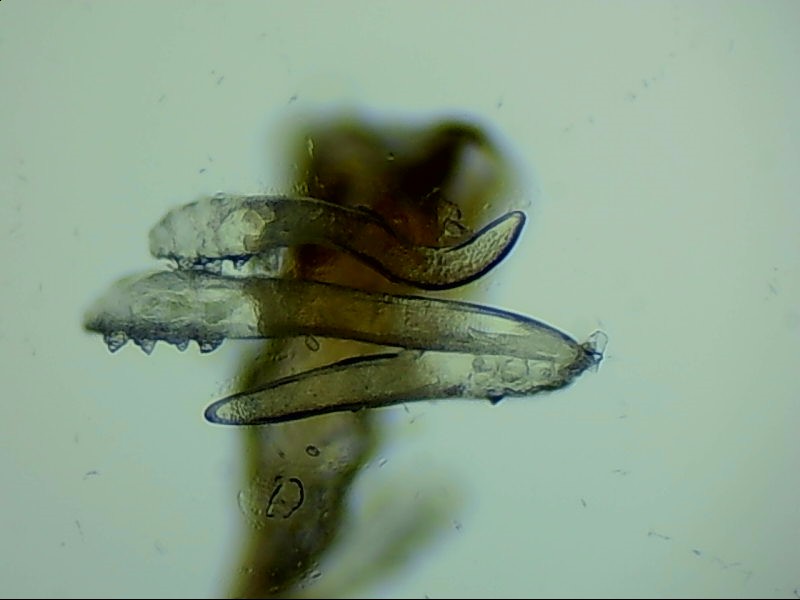

蠕形螨是螨蟲的一種,主要寄居在毛囊中。蠕形螨以分泌的油脂、分泌物為食,所以眼部寄居著蠕形螨的患者多有亂睫或睫毛脫落的癥狀。

蠕形螨寄居后,它們以睫毛毛囊里面的油脂為食。隨著油脂的缺失,睫毛會(huì)長(zhǎng)的東倒西歪,如果毛囊里的油脂都被吃光了,就會(huì)出現(xiàn)睫毛脫落這種蠕形螨性瞼緣炎的典型癥狀。

身體健康時(shí),蠕形螨就吃吃油脂,夜里爬出來活動(dòng)、交配,與我們相安無事,一旦身體的免疫力下降,蠕形螨的活動(dòng)、產(chǎn)的卵、排泄的廢物和分泌的分泌物都會(huì)引起過敏反應(yīng)。患者會(huì)出現(xiàn)眼癢、異物感、眼干、瞼緣充血、鱗屑、睫毛根部袖套狀分泌物及睫毛脫落等癥狀,嚴(yán)重者可并發(fā)結(jié)膜及角膜病變,給生活帶來不便和困擾。